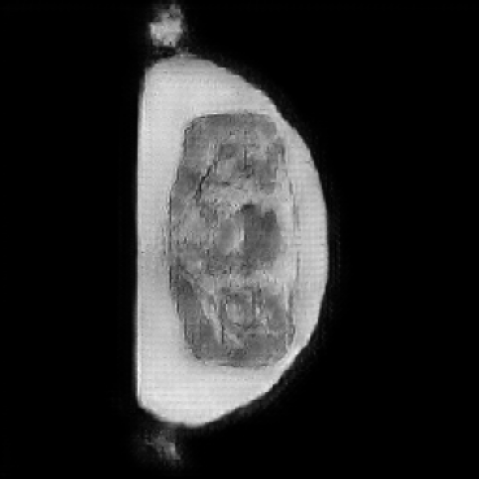

As shown in Figure 5, the generated slices exhibit high consistency across adjacent slices. The anatomical structures and semantic patterns are smoothly and coherently preserved between slices, indicating that our model is capable of generating 3D-consistent synthetic images rather than isolated 2D slices.

In our approach, we employ a compression factor of 4 to encode 3D medical images into the latent space. This level of compression reduces the spatial resolution of the original image (e.g., from 256×256 to 64×64 per slice), while still preserving the essential anatomical structures and semantic content. The latent representation at this scale offers a favorable trade-off between dimensionality reduction and semantic fidelity. Specifically, although fine-grained textures are simplified, key structural patterns (e.g., organ boundaries, lesion shapes) remain visually distinguishable and semantically coherent. As the compression rate increases, the latent representations become progressively more abstract. With lower compression (e.g., 2× or 4×), the latent features preserve key anatomical structures and spatial layouts, making them beneficial for our semantic image synthesis task in latent space, as the model can operate on compressed representations that retain sufficient semantic information without being overwhelmed by high-frequency noise. In contrast, higher compression rates (e.g., 8× or above) lead to a loss of fine-grained details and reduced semantic fidelity. The choice of a 4× compression thus ensures that the latent features are compact and meaningful, facilitating effective conditional generation while significantly reducing computational overhead. We therefore adopt a 4× compression as a compromise between computational efficiency and semantic preservation. The corresponding 2D slices in image space and latent space are shown in Figure 7.

Figure 8 further supports these findings: the images generated by Med-LSDM preserve spatial coherence across coronal and sagittal planes, whereas those from SegGuidedDiff show noticeable inconsistencies. These artifacts likely result from the 2D nature of SegGuidedDiff, which fails to account for 3D spatial relationships. In contrast, our model’s volumetric diffusion framework inherently preserves anatomical consistency, highlighting its advanta in synthesizing high-fidelity 3D medical images.